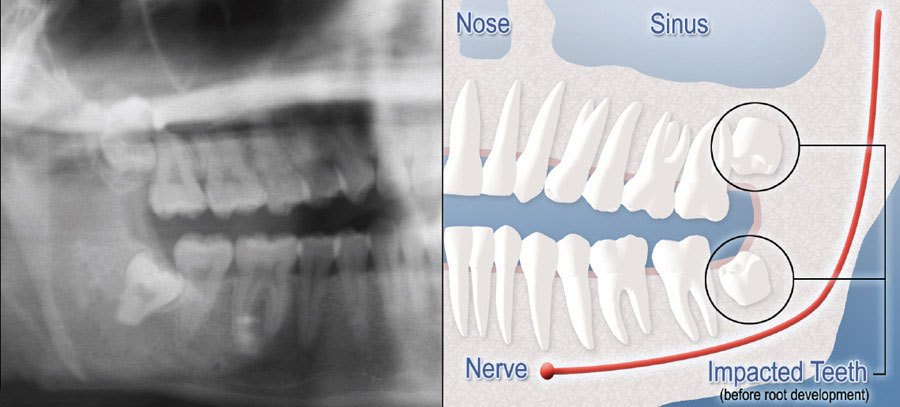

Although most people develop and grow 32 permanent adult teeth, many times their jaws are too small to accommodate the four wisdom teeth. When inadequate space prevents the teeth from erupting they are called impacted wisdom teeth. This indicates their inability to erupt into the proper position for chewing and cleaning.

We will need to see you for a consultation to determine if you will benefit from wisdom tooth removal. A special x-ray of your mouth and jaws (panorex) will be taken to determine if your wisdom teeth are impacted, if there is room for them to erupt, and how difficult it will be to have them removed.

- Complete Bony Impaction: There is NO space for the tooth to erupt. It remains embedded in the jaw bone or if even partially visible requires complex surgical techniques for removal.The impacted wisdom tooth may also be in an unusual position and difficult to remove. This situation can also arise when the shape or size of the jaw bone and other facial structures make removal of this tooth significantly more complex.